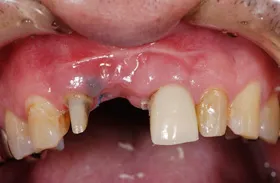

生まれつき歯が生えてこなかったケース

■治療前:生まれつき下顎左右前歯がなく隙間がある

■治療後:矯正治療後、下顎左右3番の2本にインプラント治療

| 主訴 | 生まれつき歯がなく隙間があり、審美障害・咀嚼機能障害がある |

| 治療方法 | インプラント治療 + 矯正治療 |

| 治療期間 | インプラント治療 約6ヶ月 |

| 通院回数等 | インプラント治療 約6回 |

| 費用 | 約94万円(税込) |

| リスク・副作用 | 術後の腫れ・痛み |